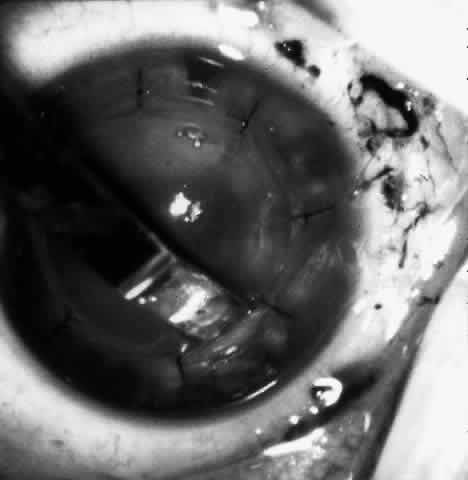

Children who have traumatic cataracts with corneal lacerations are well served by this procedure because the injury often destroys the capsular support that can be used to stabilize an intraocular lens.16–18 The epikeratophakia graft provides structural support for the weakened cornea and minimizes the induced irregular and regular astigmatism, in addition to correcting the optical error (Figs. 3 AND 4).

Fig. 4. Same patient as in Figure 11, with epikeratophakia lenticule in place 3 months after surgery. (Morgan KS, Ellis GS, Marvelli TL, Arffa RC: Epikeratophakia in children. with traumatic cataracts. J Pediatr Ophthalmol Strabismus 23:108–113, 1986)